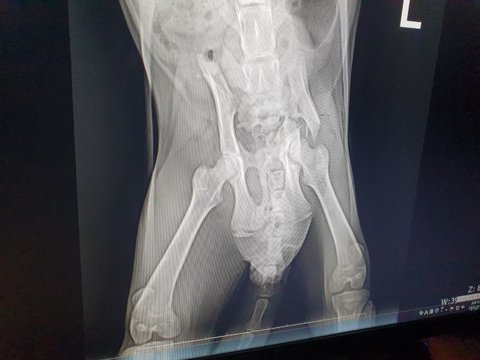

병원에 가서 진찰을 해보니 교통사고가 났던 것 같다 꼬리는 괴사해서 잘라야하고  엑스레이를 찍어보니 골반도 다쳐서 수술하지 않으면 나중엔 배변이 어렵고 CT기계가 없어 찍진 못했지만, 골반쪽이 다쳤기 때문에 신경에도 이상이 있을 것 같다 왼쪽다리도 다쳤는데 고양이가 아직 다 성장하지 못해 성장불균형이 생겨서 절뚝거리게 될 것이라 했고 수술을 하려면 엑스레이 상으로는 대략적으로 150만원정도 나올 것이라고 하였습니다.(원래 더 많이 나오는데 길고양이라서 입원비도 빼주셨습니다)

골반 왼쪽 부러짐, 오른쪽 탈골 수술을 진행하였고.

골반 수술 검사비 제외 150만원 비용 발생했습니다.